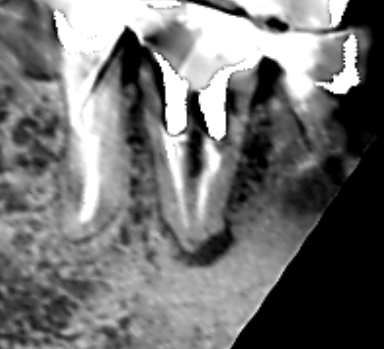

初診時の下顎第一大臼歯の冠状断のCT画像です。

矢印の先に、舌側に根の沿って長い影が認められます。歯根に沿った長い影がみられるときは、歯根破折の可能性があります。

精密根管治療6カ月後の経過観察時の冠状断のCT画像です。下顎第一大臼歯の根の舌側に拡がっていた長い膿の影が消え、歯槽骨が再生しています。膿の原因は、単なる根管治療不足でした。

本症例の膿は、歯根破折ではなく根管治療の失敗が原因でした。歯根破折が疑えるケースでも、すぐに抜歯をせず、よく精査することが重要です。歯根が割れていなければ正しく根管治療を行うことにより膿が治る可能性があるからです。